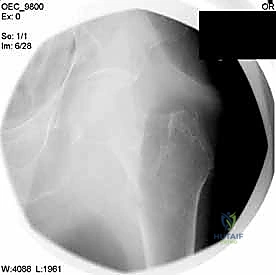

التصوير الطبي المتقدم

- الأشعة السينية (X-rays): هي المعيار الذهبي الأولي. يتم أخذ صور من الأمام للخلف (AP) وصور جانبية (Lateral) للحوض والورك المصاب. تكشف هذه الصور عن موقع الكسر، نوعه (بسيط أم مفتت)، ودرجة الإزاحة.

مجموعة من الصور الإضافية التي توضح مراحل دقيقة من العمل الجراحي المعقد الذي يجريه الأستاذ الدكتور محمد هطيف لضمان أعلى درجات الدقة الميكانيكية الحيوية: